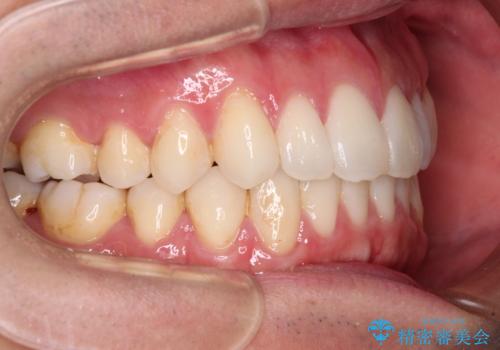

- 全体的なデコボコと、前歯の前に出ている感じを気にして来院された患者様です。

患者様と相談の上、非抜歯にてインビザラインを用いて矯正治療を行うこととし、IPR(歯と歯の間)並びに歯列全体の後方移動により口元の突出感の改善することとしました。

お仕事が忙しい方で、装着時間が不足したり、定期的な通院ができなかったりと、自己管理が重要なインビザラインによる矯正治療が長期化する要因が重なり、5年ほどの期間を要しました。